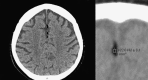

Intracranial lipomas are described as a rare finding. In this small retrospective analysis of 50 cases undergoing brain CT for various reasons small intracranial lipomas where found in nine patients. In contrast to previous reports lipomas may be a frequent finding on CT imaging of the brain. In particular, these small lipomas seem to be incidental findings lacking clinical relevance. Radiologists should be aware of intracranial lipomas to establish proper differential diagnosis.